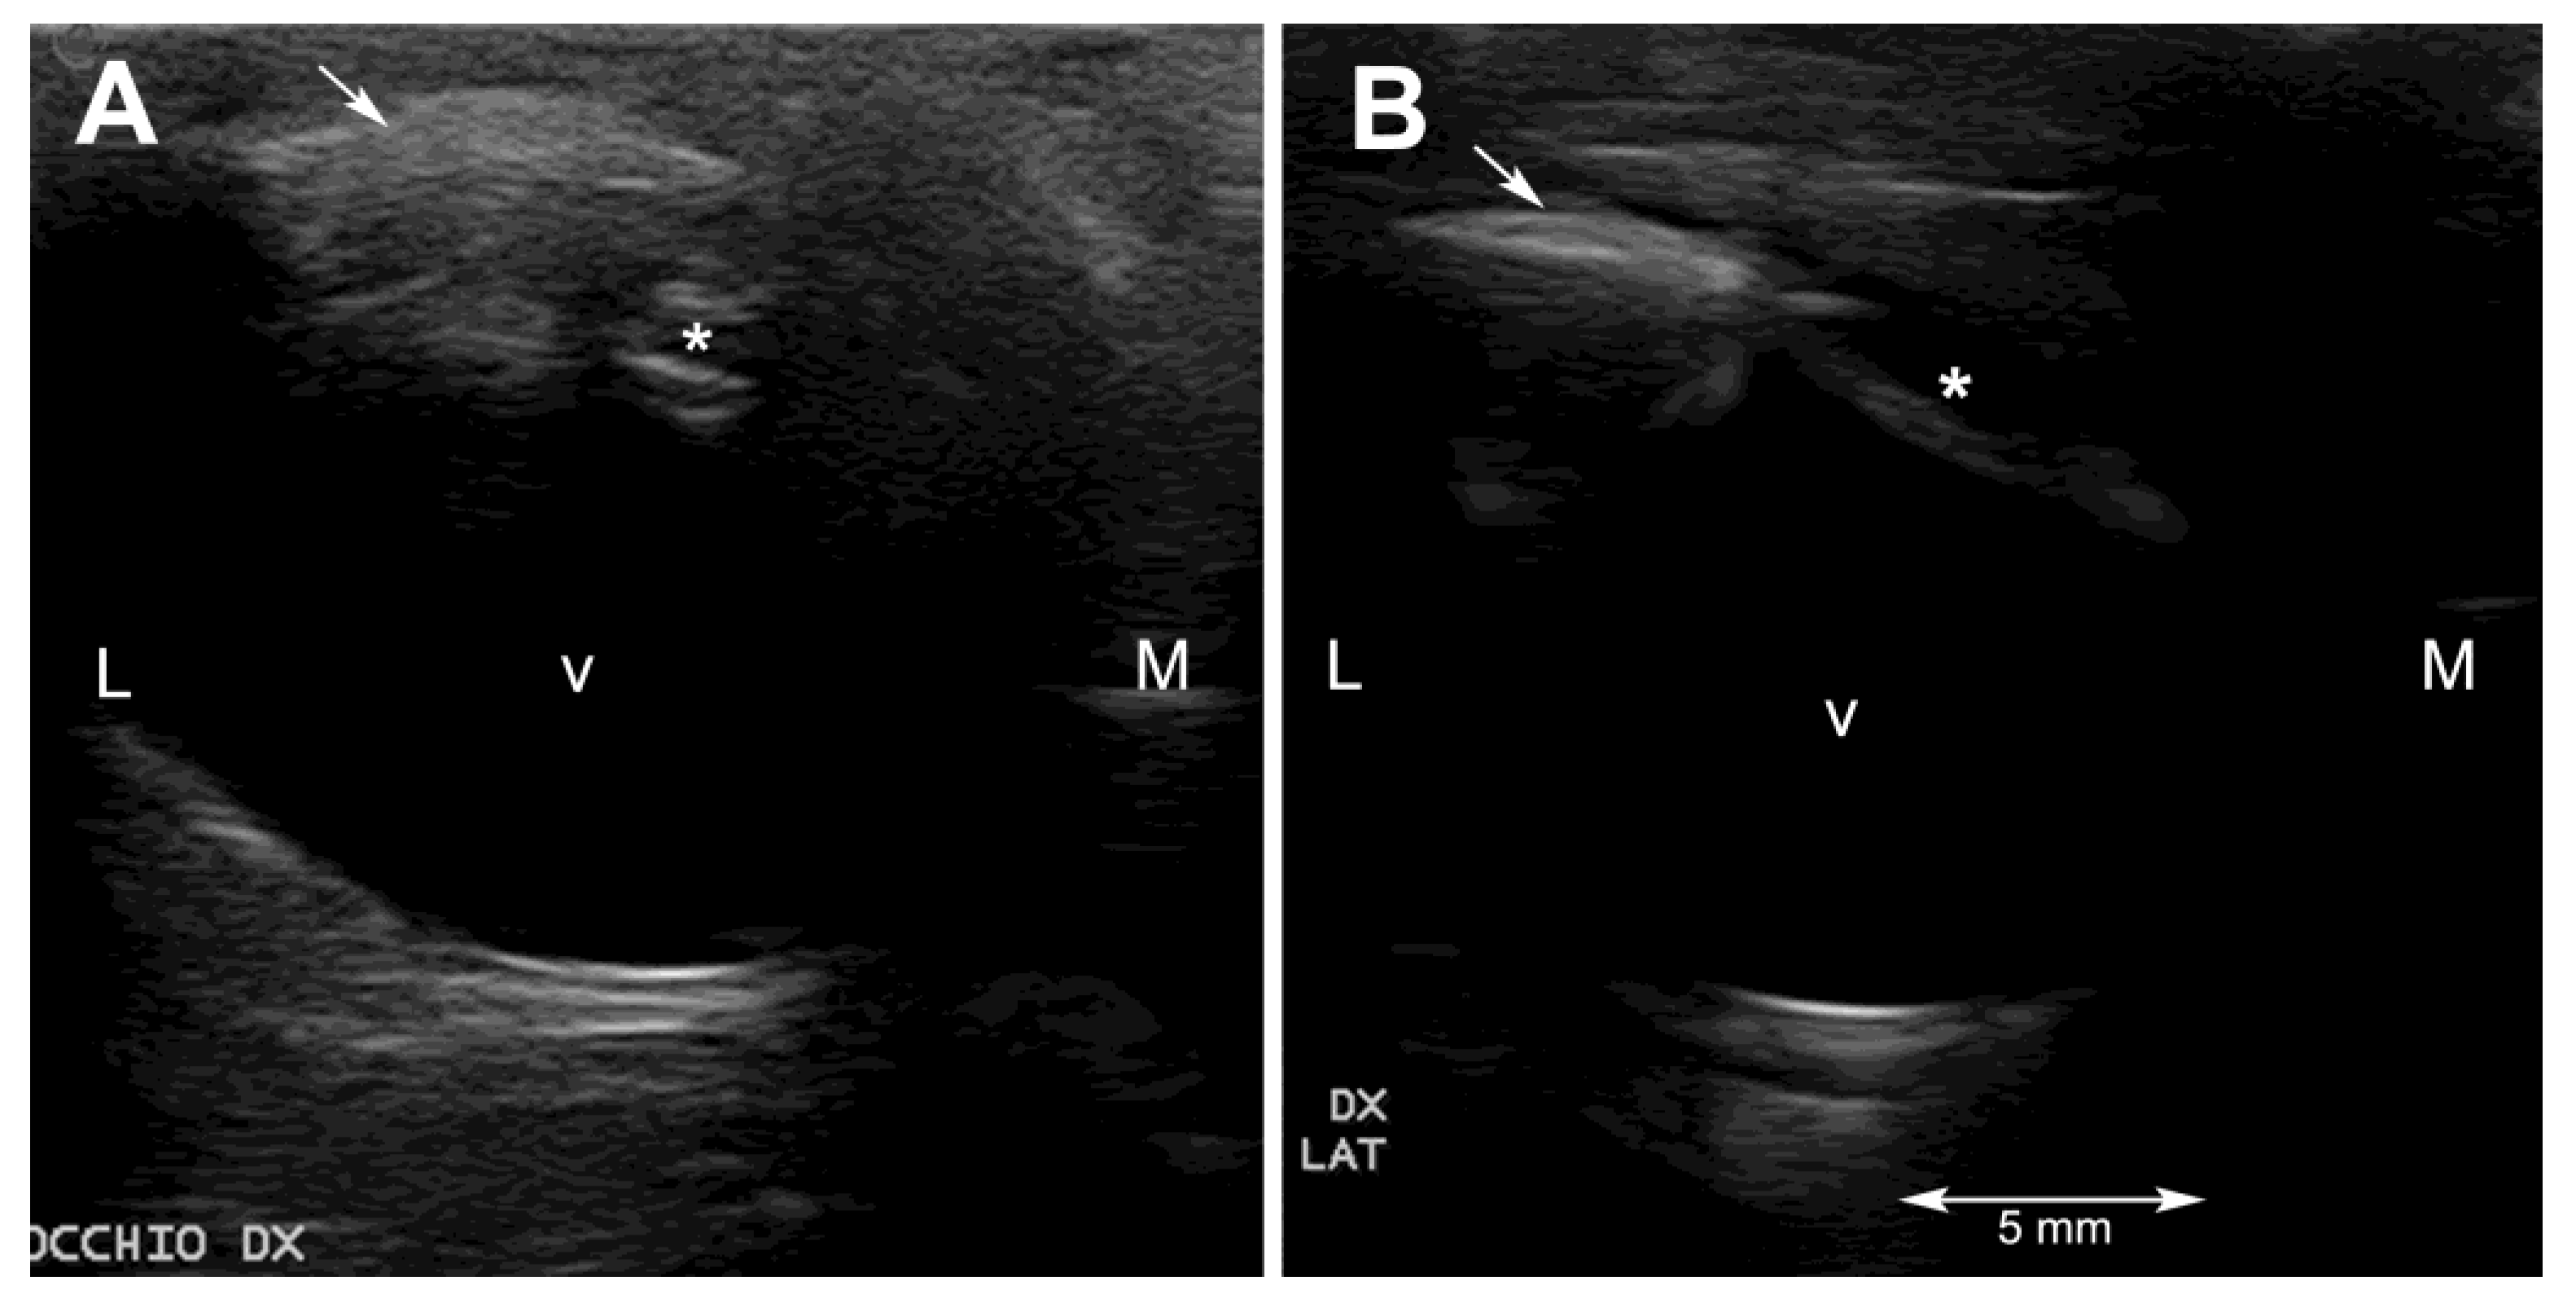

2.3. Ultrasonography

Ultrasonography was performed on sedated turtles. The sedation was obtained by administering IM 0.05 mg/kg medetomidine chlorhydrate (Dormilan 1 mg/mL—ATI srl, Italy). Ultrasonography (US) examination was performed using a general purpose US device (MyLab Class C, Esaote, Genova, Italy) equipped with a high frequency linear probe (14 MHz), connected to the cornea through a copious amount of sterile gel (Sterile Aquasonic 100, Parkers Lab., Fairfield, NJ, USA) as previously described [23]. Despite the small size of the eyeballs of these two turtles and the thinner anterior chamber and smaller lens, characteristic of this species, it was possible to visualize all the anatomical structures of the eye. In particular, the lens was echoic instead of the normal anechoic pattern (Figure 2A and Figure 3A).

Ultrasonographically, the turtles were examined one month and 6 months after the surgery. Both animals showed a hypoechoic anterior and posterior chamber without any visible lesions to the eyeballs at the first check, and no changes were seen at the last examination (Figure 2B and Figure 3B).

Ultrasonography helped to rule out lesions to the vitreal body and to the retinal layer. The ultrasonographic exam allowed visualization of the echoic cataractous lens and its modifications after the surgery. The main difficulties during the ultrasonographic exams were, other than the very small size of the eyeball, reverberation artifacts, resulting from the presence of the scleral ossicles, and the retraction reflex, which is very pronounced in this species.

Figure 2. Ultrasonographic horizontal scan of the right eyeball of subject 1 (Alessia) before (A) and six months after the surgery (B). At the last ultrasonographic exam, the lens appears hypoechoic but thinner than normal. Legend: * = lens; arrow = scleral ossicle; v = vitreal body; L = lateral; M = medial.